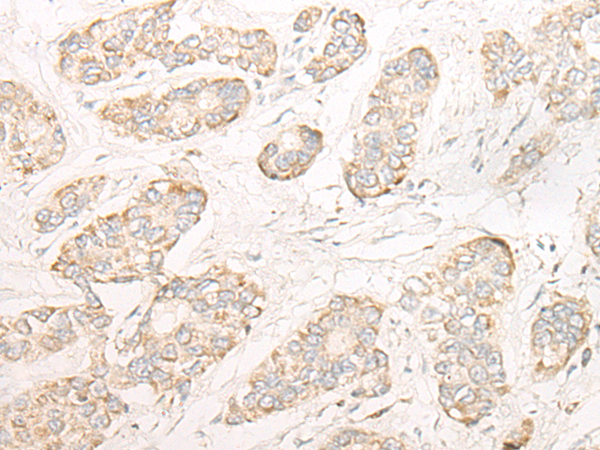

分类: 科研抗体货号: P09631别名: ELA3; ELA3A应用: IHC反应种属: Human